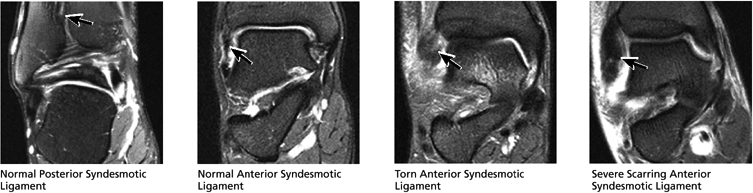

The syndesmotic ligaments consist of the anterior syndesmotic or anterior inferior tibiofibular ligament and the posterior syndesmotic or posterior inferior tibiofibular ligament, the interosseous membrane, and the transverse tibiofibular ligament.

FIGURE 5.27 ● Axial anatomy of the ankle and foot. (A) The flexor digitorum longus, flexor hallucis longus, peroneus brevis, soleus, and extensor digitorum muscles are examined at this level for strain, tears, or fatty atrophy that may suggest denervation. (B) The tibialis anterior, extensor hallucis longus, and extensor digitorum longus tendons are examined on every ankle MR examination. Extensor tendon pathology is frequently overlooked if these tendons are not included as part of the ankle checklist. (C) Tears and sprains of the anterior syndesmotic ligament are a frequent cause of persistent ankle pain following ankle sprain. The syndesmotic ligaments are thick, tough ligaments that are important ankle stabilizers, and delayed diagnosis of syndesmotic tears may result in significant degenerative arthrosis at the tibiotalar joint due to the resulting ankle instability. The syndesmotic ligaments course obliquely inferiorly from the tibia to the fibula and are not usually visualized in their entirety on a single axial image; rather, their course is followed on at least two or three successive axial images. (D) The peripheral margin of the peroneal tendons and tibialis posterior tendon should normally never extend beyond the peripheral margins of the lateral and medial malleoli, respectively. Tendon subluxation around the posterior corner of either malleolus is indicative of a tear of the overlying flexor retinaculum (medially) or peroneal retinaculum (laterally). When the retinacula are torn, the tendon is free to intermittently sublux or dislocate, leading to tendon degeneration, pain, and tendon dysfunction. (E) Suspected osteochondral lesions of the talar dome are visualized and further characterized on axial images through the top of the talar dome. (F) The peroneus brevis tendon may normally appear somewhat flattened. However, as the tendon degenerates, it becomes U-shaped and drapes around the anterior aspect of the peroneus longus and becomes impinged between the peroneus longus tendon and the lateral malleolus. With further degeneration, the peroneus brevis may split or completely rupture. (G) Evidence of anterior talofibular ligament injury is visualized on the majority of MR ankle examinations and appears as thickening, intermediate signal with ill-defined fibers, or attenuation of the ligament. This is commonly asymptomatic. (H) Because the flexor hallucis longus tendon sheath communicates with the tibiotalar joint, fluid may normally be present within the tendon sheath in proportion to the amount of fluid in the tibiotalar joint. If there is fluid within the tendon sheath out of proportion to that seen in the tibiotalar joint, tenosynovitis is most likely present. The finding of flexor hallucis longus tenosynovitis should prompt a search for an os trigonum, as impingement of the flexor hallucis longus tendon between an os trigonum and the posterior tibial plafond is a common cause for FHL tenosynovitis. (I) The calcaneofibular ligament (CFL) passes anterior and medial to the peroneal tendons. On the image at which the CFL passes directly medial to the peroneus brevis tendon, the appearance of the peroneus brevis and the CFL side by side is occasionally mistaken for a split peroneus brevis tendon. (J) Dilated posterior tibial veins within the tarsal tunnel occasionally compresses the tibial nerve. In the setting of clinical suspicion for tarsal tunnel syndrome or if there is evidence of muscle denervation on MR images, the size of the posterior tibial veins should be described. (K) The spring ligament is identified at this axial image location, extending from the anteromedial calcaneus to the posteromedial navicular. Tears of the spring ligament may result in medial instability and hindfoot valgus. (L) The posterior tibialis tendon (PTT) may normally become thickened and fan-like as it passes posterior to its navicular insertion (prior to also inserting on the cuneiforms and the base of the second through fourth metatarsals). In the absence of other findings, the thickening of the PTT at this level should not be mistaken for focal tendinosis. (M) On inferior images through the ankle, Lisfranc's ligament is occasionally included in the FOV. Lisfranc's ligament extends from the medial cuneiform to the base of the second metatarsal. If Lisfranc's ligament is included in the FOV, the status of the ligament should be described, as undiagnosed Lisfranc ligament tears can lead to debilitating midfoot arthrosis. (N) As the medial and lateral tendons turn from their vertical course to a horizontal course along the plantar aspect of the foot, the tendons may demonstrate a magic-angle artifact, causing the tendons to appear gray on short-TE images, mimicking tendinosis. Correlation with images using longer TE values is advised in such situations.